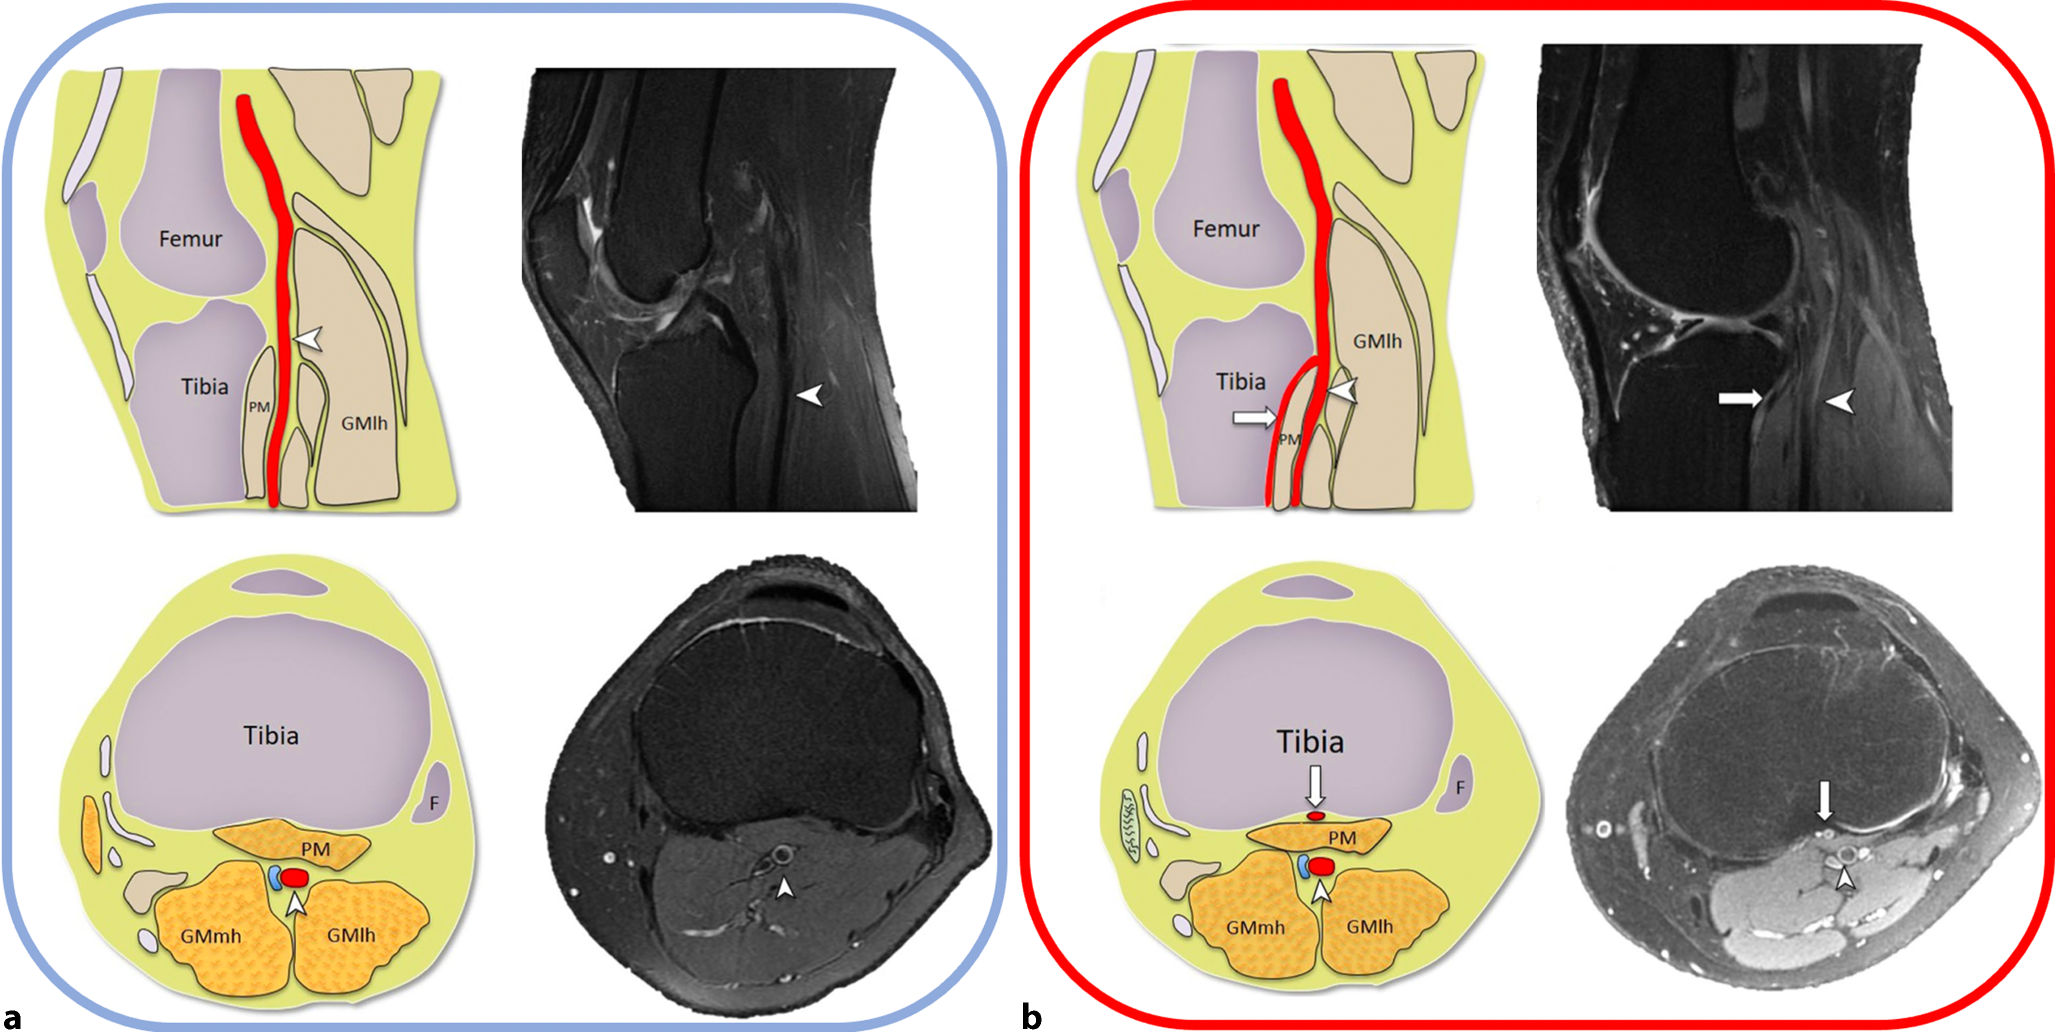

Ein Pseudoaneurysma der A. poplitea nach HTO ist eine seltene Komplikation und wurde bisher nur in einzelnen Fallberichten beschrieben [2, 3, 6]. Der Verlauf und die Varianten der Aufteilung der A. poplitea müssen genau analysiert werden, um diese Komplikation besser zu verstehen. Im Regelfall geht die A. tibialis anterior aus der A. poplitea dorsal des M. popliteus ab, sodass dieses Gefäß während der Osteotomie nicht nur durch den Weichteilretraktor, sondern auch durch den M. popliteus geschützt wird. Bei der Normvariante mit hoch aberrantem Abgang der A. tibialis anterior aus der A. poplitea verläuft die A. tibialis anterior ventral vom M. popliteus und in unmittelbarer Nachbarschaft zum posterioren Kortex der proximalen Tibia (Abb. 6). Somit ist das Gefäß während der Osteotomie deutlich mehr gefährdet.

Abb. 6

a Schematische axiale Darstellung der normalen Knieanatomie und axiale MRT der normalen Knieanatomie, die die A. poplitea (Pfeilspitze) zeigt. Die A. poplitea verläuft dorsal des M. popliteus (PM) und der Abgang der A. tibialis anterior aus der A. poplitea befindet sich weiter distal, b schematische axiale Darstellung und axiale MRT-Aufnahme des Knies zeigen die hoch aberrante Normvariante der A. tibialis anterior (weißer Pfeil) zwischen dem posterioren Kortex der proximalen Tibia und ventral des M. popliteus. Fibula (F), M. gastrocnemius Caput mediale (GMmh), M. gastrocnemius Caput laterale (GMlh). (Aus: [5])